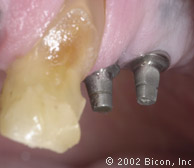

2. | 拔除双尖牙前的颊侧观。 |